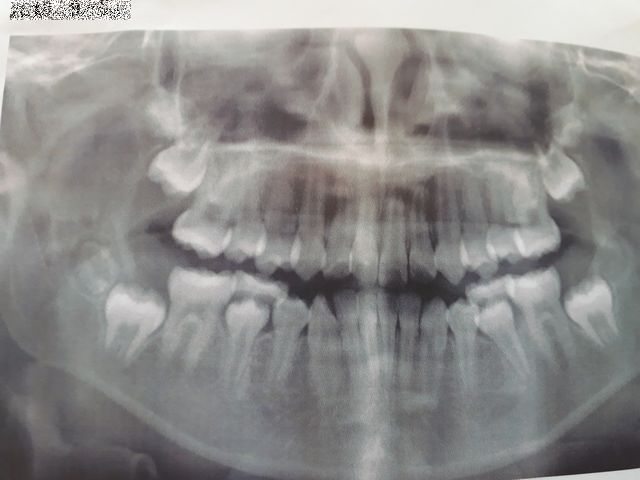

《いぬ》の矯正歯科に行きました。ヘッドギアを使い永久歯が生えるスペースを確保しました。